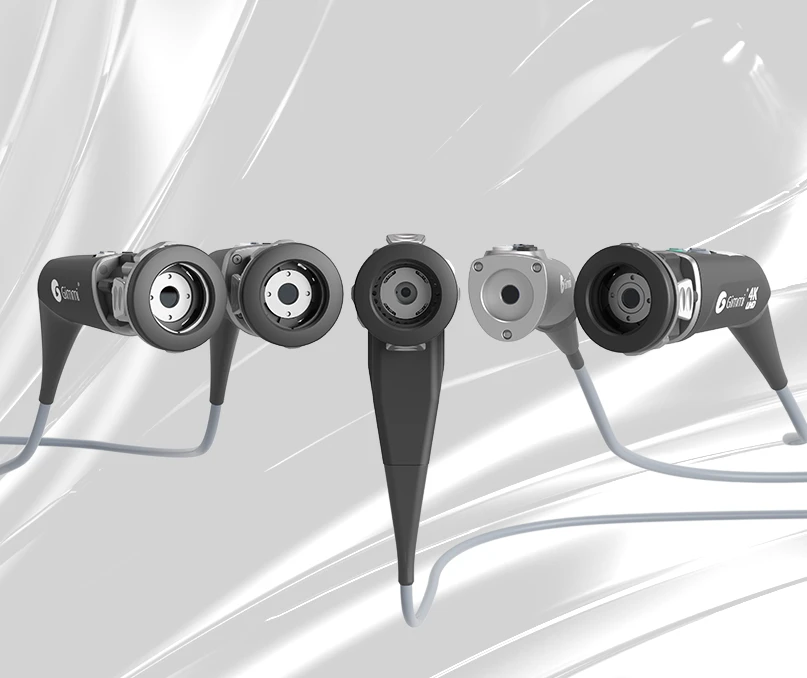

Sempre adattabile cambiando le teste della telecamera

La gamma di soluzioni di telecamere disponibili varia dal Full HD al 4K UHD – già questo offre molto all’occhio. È possibile regolare le prestazioni del sistema in qualsiasi momento sostituendo la testa della telecamera.

Modulare nella progettazione –

Un'unica piattaforma, cinque possibilità

The AlphaSMART system is designed to be flexibly configured – by simply swapping the camera head, surgical teams can tailor the imaging setup to the specific needs of each procedure. This modular concept is centered around the AlphaSMART Cam+, which supports five specialized camera heads – ranging from Full HD to 4K UHD, including pendulum-style, 4K NIR, and fully autoclavable variants.

Teste della telecamera AlphaSMART – soluzioni su misura per ogni scenario chirurgico

Scoprite l’imaging chirurgico al suo meglio. La gamma di teste della telecamera AlphaSMART offre un’ampia scelta di teste ad alte prestazioni, dal Full HD al 4K UHD, garantendo colori brillanti e una qualità dell’immagine ottimale in ogni procedura.

Progettate per garantire flessibilità e facilità d’uso, queste teste telecamera supportano varie applicazioni cliniche con caratteristiche quali zoom ottico, diversi pulsanti di comando con funzioni liberamente assegnabili, un accoppiatore TV integrato e un design adatto alle procedure di ricondizionamento.

Cinque teste telecamera – su misura per la vostra routine chirurgica

Per soddisfare le diverse preferenze ed esigenze, il sistema AlphaSMART include cinque modelli distinti di teste di telecamera. Ogni variante è ottimizzata per casi d’uso specifici: